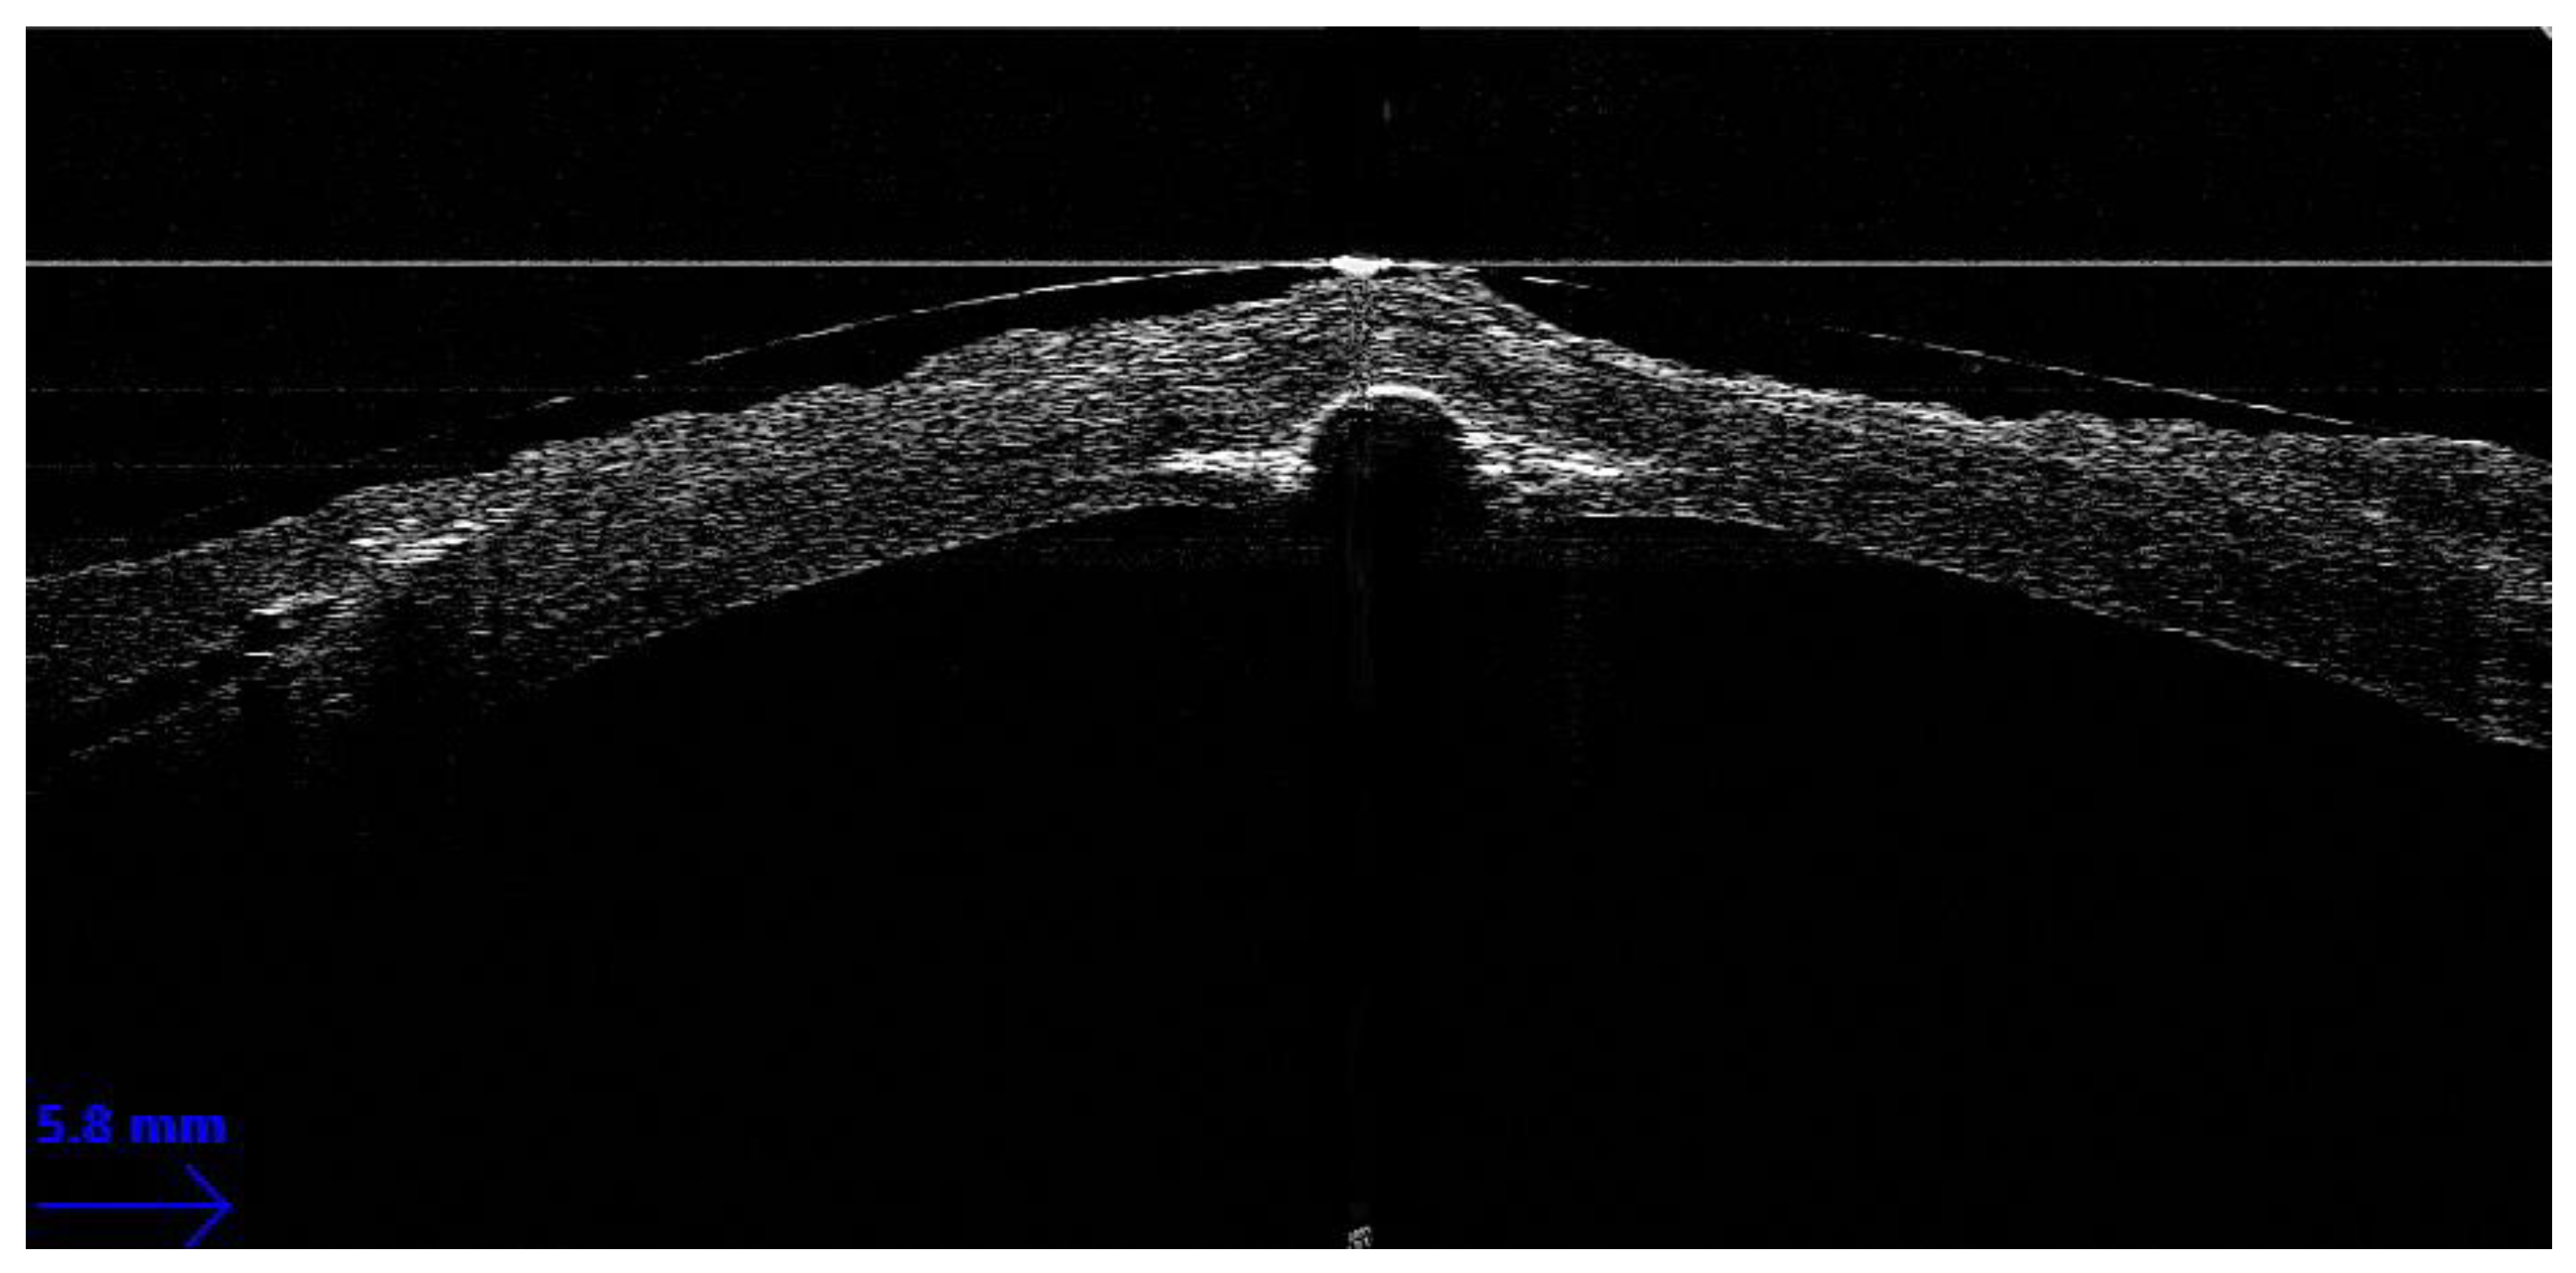

Guiding Big-Bubble Deep Anterior Lamellar Keratoplasty (BB-DALK)

- Scorcia, V.; Busin, M.; Lucisano, A.; Beltz, J.; Carta, A.; Scorcia, G. Anterior Segment Optical Coherence Tomography–Guided Big-Bubble Technique. Ophthalmology 2013, 120, 471–476. [Google Scholar] [CrossRef] [PubMed]

- Myerscough, J.; Friehmann, A.; Busin, M.; Goor, D. Successful Visualization of a Big Bubble during Deep Anterior Lamellar Keratoplasty using Intraoperative OCT. Ophthalmology 2019, 126, 1062. [Google Scholar] [CrossRef] [PubMed]

- Altaan, S.L.; Termote, K.; Elalfy, M.S.; Hogan, E.; Werkmeister, R.; Schmetterer, L.; Holland, S.; Dua, H.S. Optical coherence tomography characteristics of different types of big bubbles seen in deep anterior lamellar keratoplasty by the big bubble technique. Eye 2016, 30, 1509–1516. [Google Scholar] [CrossRef] [PubMed]

- Steven, P.; Le Blanc, C.; Lankenau, E.; Krug, M.; Oelckers, S.; Heindl, L.M.; Gehlsen, U.; Huettmann, G.; Cursiefen, C. Optimising deep anterior lamellar keratoplasty (DALK) using intraoperative online optical coherence tomography (iOCT). Br. J. Ophthalmol. 2014, 98, 900–904. [Google Scholar] [CrossRef] [PubMed]

- Au, J.; Goshe, J.; Dupps, W.J.; Srivastava, S.K.; Ehlers, J.P. Intraoperative Optical Coherence Tomography for Enhanced Depth Visualization in Deep Anterior Lamellar Keratoplasty from the PIONEER Study. Cornea 2015, 34, 1039–1043. [Google Scholar] [CrossRef]